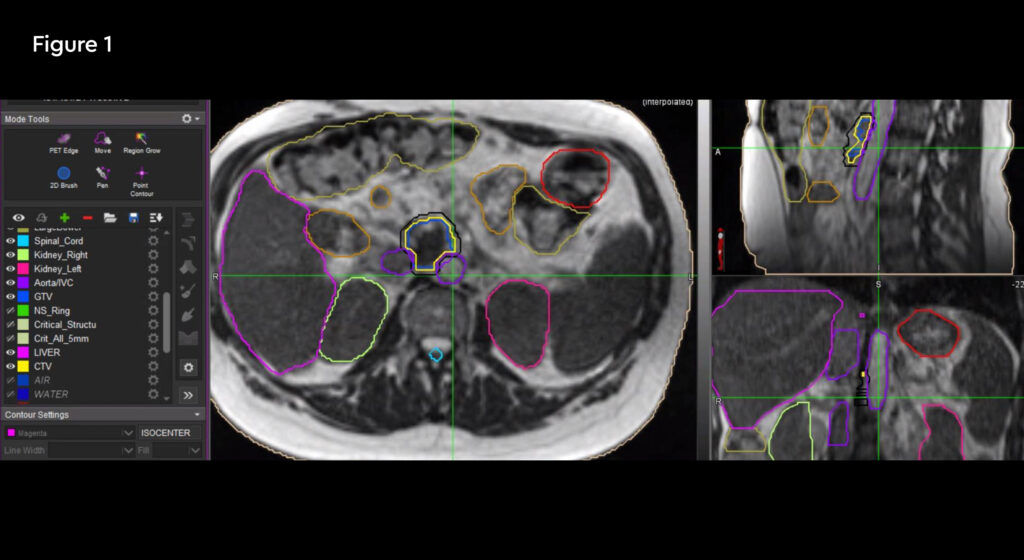

MRIdian treatment

SABR treatment on the MRIdian was prescribed at 36.25 Gy in five fractions. The aim of treatment was curative.

At each session, daily adaptation was performed to account for changes in the position of the prostate and for variable bladder and bowel filling. Figure 1 and figure 2 illustrate the typical differences seen between the original planning MRIdian scan and that seen on the day of treatment due to day-to-day organ movement. Figure 3 and figure 4 illustrate how these movements were accommodated with the on-table plan adaptation.

Fig 1: Original planning MRIdian scan

Fig 2: MRIdian scan at fraction 3, prostate position changed due to larger rectal diameter secondary to gas and smaller bladder

Fig 3: Prostate SABR delivery plan. Prostate volume covered by 95% isodose (green line, red arrow). Tight conformality at rectal/prostate boundary (white arrow), and rapid drop off of high dose (50% isodose, green line, green arrow) to optimise dose delivery to the prostate and limit dose to the rectum, reducing the risk of toxicity

Fig 4: Fraction 3, adapted plan, optimised for anatomy of the day. Prostate volume covered by 95% isodose (green line, red arrow). Tight conformality at rectal/prostate boundary (white arrow), and rapid drop off of high dose (50% isodose, green line, green arrow) to optimise dose delivery to the prostate and limit dose to the rectum, reducing the risk of toxicity

Each treatment including set-up and plan adaptation took 45 to 60 minutes during which time the patient was on the bed. As the patient was local to the treatment centre in Oxford he was easily able to attend the sessions and treatment was completed within two weeks.